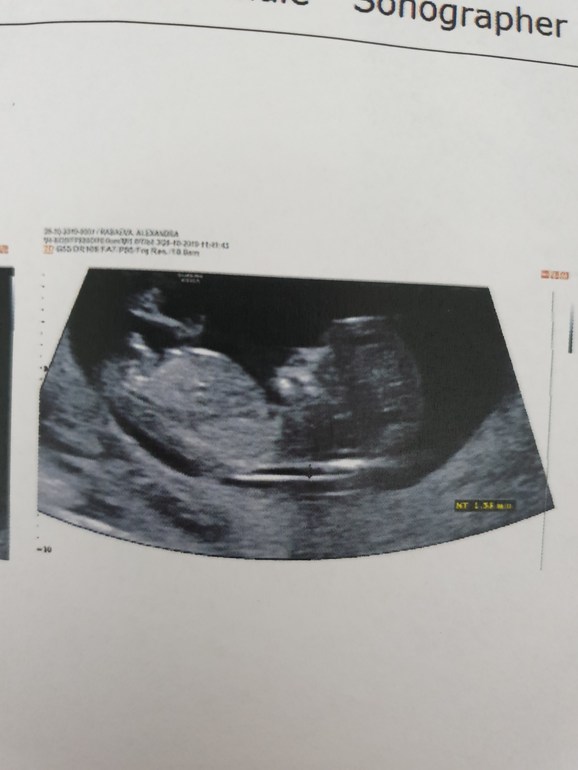

12+ 4 ! Скрининг, ощущения , фото 😍

Результаты: УЗИ, КТГ, доплера, скринингаНу вот, дождалась я этого скриринга! В первую Б не делала его и даже не собиралась делать, а тут дождаться не могла! И так!

По УЗИ все хорошо- как мы выросли за неделю!!! Догнали сроки. По развитию поставила пдр 7 мая, если ПКС то 1 мая. Любовалась малышастиком минут 30🤗 все разглядели, и ручки, и ножки ,и УшкИ😍 поспал, покрутился, головку почасал, дал полюбоваться собой со всех сторон ❤

А вот и мы